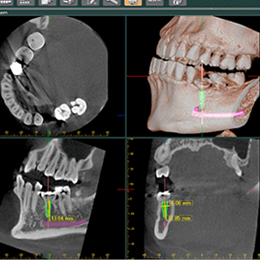

〔歯科用CT〕

より高度な診断と安全な治療のために、当院では歯科用CTを導入しています。一般歯科治療からインプラント治療に至る、あらゆる治療の診断に使用しております。また、撮影範囲を限定しているためX線低被爆でのCT撮影が可能です。

歯科用CTとは

近年開発された歯科に特化したCT撮影装置で、コーンビームCTとも呼ばれています。

歯科用CTの撮影は、コーンビームが1回転するだけなので、撮影時間が10秒足らずと短く、被ばく線量も医科用CTに比べて8分の1から50分の1と少なくて済みますし、高画質で繊細な画像を得ることができます。

従来のX線と比べると

2次元の平面的な画像でしたが、CTでは3次元の立体的な画像で診断ができるため、骨の形や密度、神経の走行状態、また歯の根の先の病巣の位置や大きさなどが正確に把握できるようになりました。

これは安全性の高い治療につながります。

インプラント治療

インプラントを埋入する部位の骨の状態(骨質、厚み、高さ、形態)や神経や血管の走行がわかるので、診断が正確になりました。